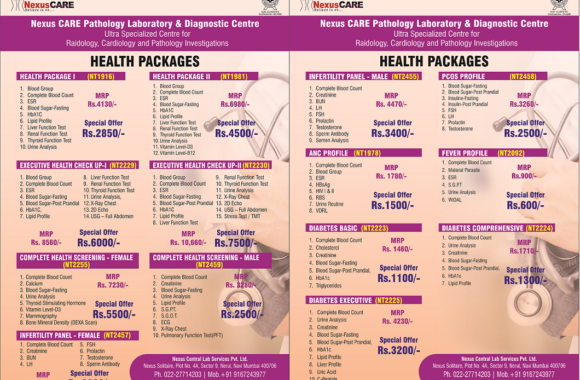

OUR SERVICES

VIEW ALL - 31 March 2023 by admin, in Services